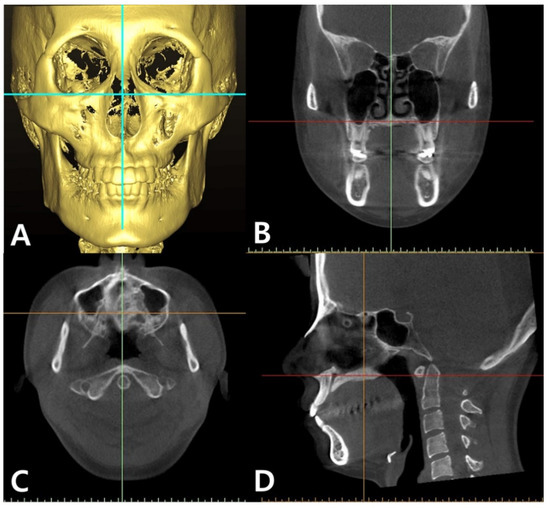

A CBCT Evaluation of Midpalatal Bone Density in Various Skeletal Patterns